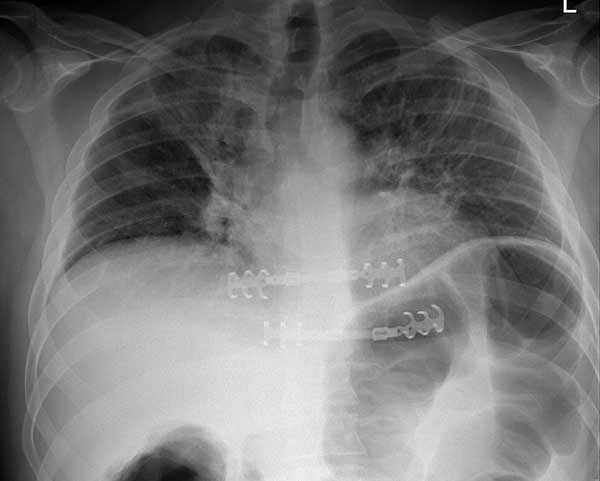

- Functional repair of chest wall abnormalities (for example, pectus excavatum) (Figures 6-8)

Many different methods have been proposed to stabilize the chest wall after resection. The rigid reconstruction of chest wall defects with GORE-TEX® felt or mesh-cement sandwiches has been widely reported. However, it does not restore normal chest wall mechanics and is vulnerable to catastrophic prosthetic infections. We believe that the application of these newer surgical materials is likely to provide important clinical benefits over established techniques. It is also an advantage that the same techniques can be applied to a number of clinical scenarios. We are particularly interested in their use in massive chest wall trauma, where early restoration of chest wall mechanical integrity may well play a part in reducing respiratory morbidity. We treated 9 patients (4 pectus corrections, 3 chest wall resections for malignancy, 1 flail chest fixation and 1 chronic pain syndrome from rib malunion) with excellent results.

Here we present, as a paradigm of repair, the case of a 65 year old gentleman referred to our institution for an indolent mass in the left anterior chest wall. Repairs for other conditions follow the same rules. This mass had been stable in size for more than 12 months and the patient was prompted to seek medical attention as, after weight loss due to dieting, he felt the mass was uncomfortable while sleeping. Apart from coronary stenting for angina, the past medical history was unremarkable.

Computed tomography scan of the chest showed a mass protruding from the cortex of the third rib. A percutaneous core biopsy was non-diagnostic. We proceeded to an open incisional biopsy. This was reported as showing a spindle cell neoplasm. The patient was therefore scheduled, after multidisciplinary meeting discussion, for radical surgery.

At surgery, the mass was arising from the cortex of the third rib, and solid measuring 5x8 cm. There was no macroscopic involvement of the surrounding extra-thoracic musculature or of the underlying lung, the mass being confined to the rib and intercostal muscles. The patient underwent resection of the second to fourth ribs and the rhomboid muscle as well, in the attempt to get clear margin. The large antero-lateral defect was eventually reconstructed using 2 mouldable titanium bars. To prevent lung herniation through the defect, we reconstructed the layers anatomically using a biological patch (Veritas®). The final histopathology was a low grade sarcoma of the chest wall with clear resection margins.

He made an excellent recovery with daily physiotherapy to encourage shoulder movements. He was discharged with oral analgesia on postoperative day 4. At 1-month follow-up the patient had no pain at all, discontinued analgesia on postoperative day 17 and demonstrated a full range of shoulder movement. His chest x-ray was unremarkable and the wound healed without complication.